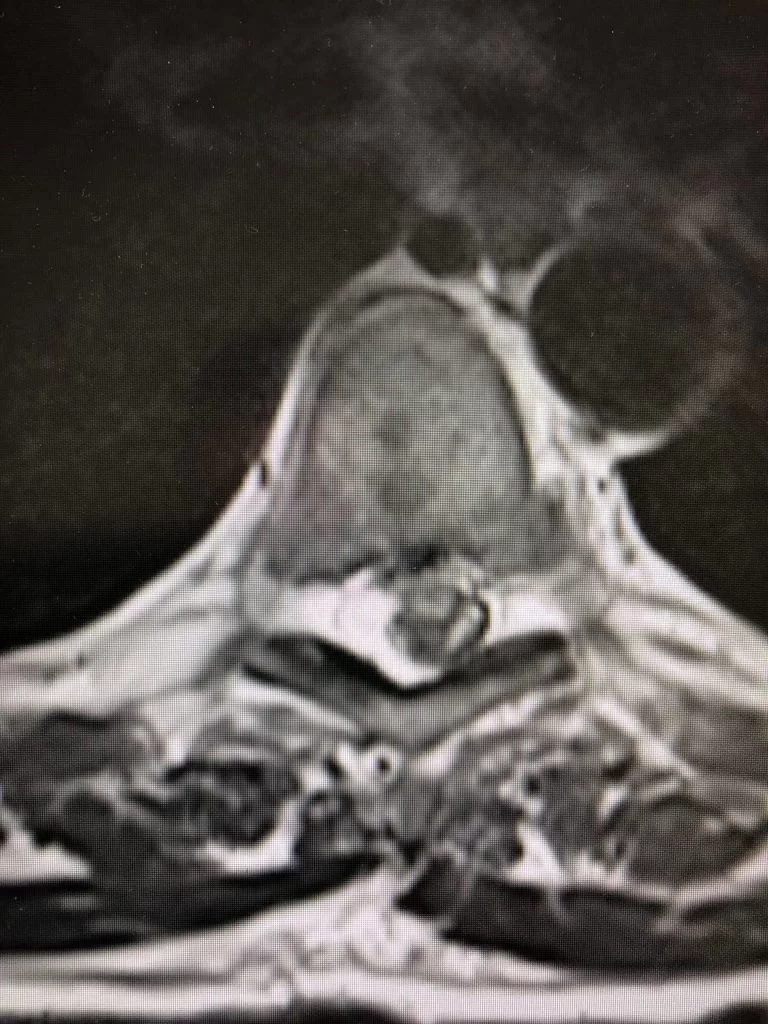

Ο απεικονιστικός έλεγχος ανέδειξε δύο επασβεστωμένες θωρακικές δισκοκήλες στο ύψος Θ6/7 και Θ7/8.